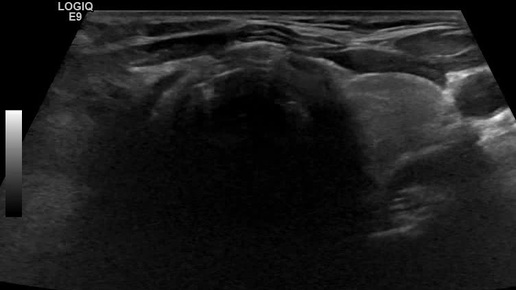

Видео к статье "Стратификация узлов щитовидной железы. TI-RADS-4" https://dzen.ru/a/ZwNx-uQp-Sfk6L46

Ультразвуковые находки от врача УЗД Зорина Я.П.